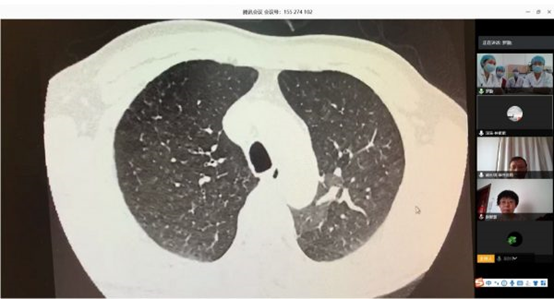

北阜和深阜肺血管病房在线查房

根据卫健委新冠肺炎疫情防控工作总体部署以及医院要求, 3月16日,北阜肺血管与血栓一病区和深阜肺血管病房已同步开始有序收治患者,开展包括右心导管、肺动脉造影及慢性血栓栓塞性肺动脉高压患者的肺动脉球囊扩张术等手术在内的肺血管病所有诊治。为减少新冠肺炎疫情传播风险,保证深圳肺动脉高压患者得到最佳诊疗方案,北阜和深阜两地肺血管病房充分利用“互联网+医疗”的优势作用,开展远程线上查房,对每位患者资料进行详细分析,确定诊治方案,使深圳的患者在疫情特殊时期可得到与平时同样的医疗服务。